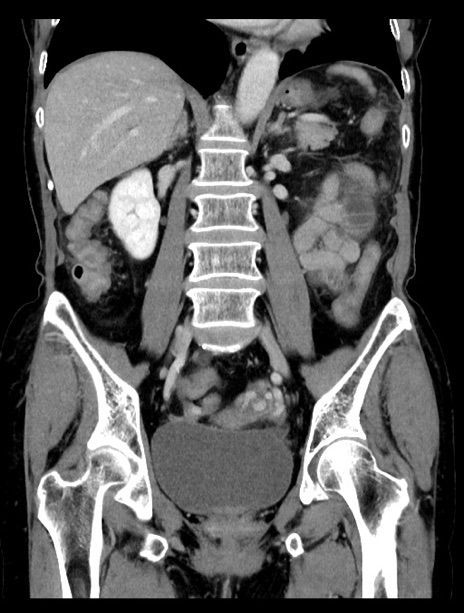

症例23(冠状断像)

【症例】70歳代女性

【主訴】下腹部痛・嘔吐

【現病歴】2日前より腹痛あり。昨日嘔吐あり。症状改善しないため来院。

【既往歴】胃GISTに対して胃部分切除後。

【身体所見】BT 37.1℃、BP 128/77mmHg、腹部:平坦・軟、下腹部に圧痛あり。

【データ】WBC 10200、CRP 0.31